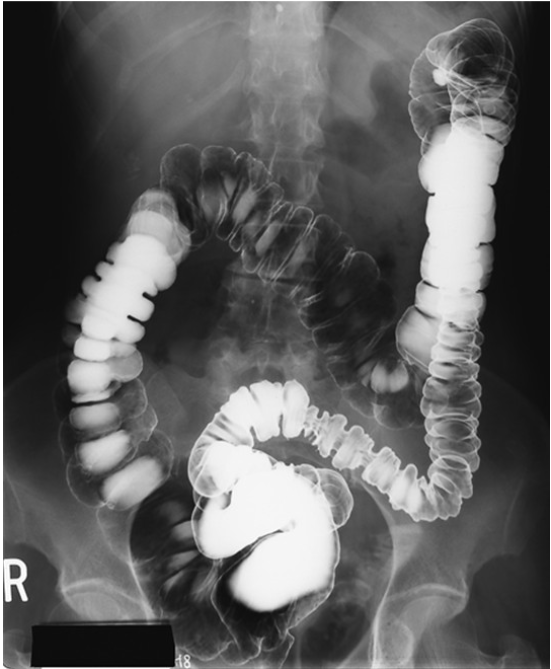

What contrast procedure was performed to produce this image?

Air-Contrast Barium Enema (ACBE)

1)What does single contrast mean in the first image?

2)What does double contrast mean in the 2nd image?

3)contrast media used for this examination?

4)the 3 contraindications of the contrast used?

1)entire colon is filled only with barium sulfate (this is a BE)

2)both barium sulfate and air. (this is a ACBE)

3)Barium Sulfate

4)DON’T us if suspected bowel perforation; Bowel obstruction (high risk of retention or perforation);

Pre- or post-surgy